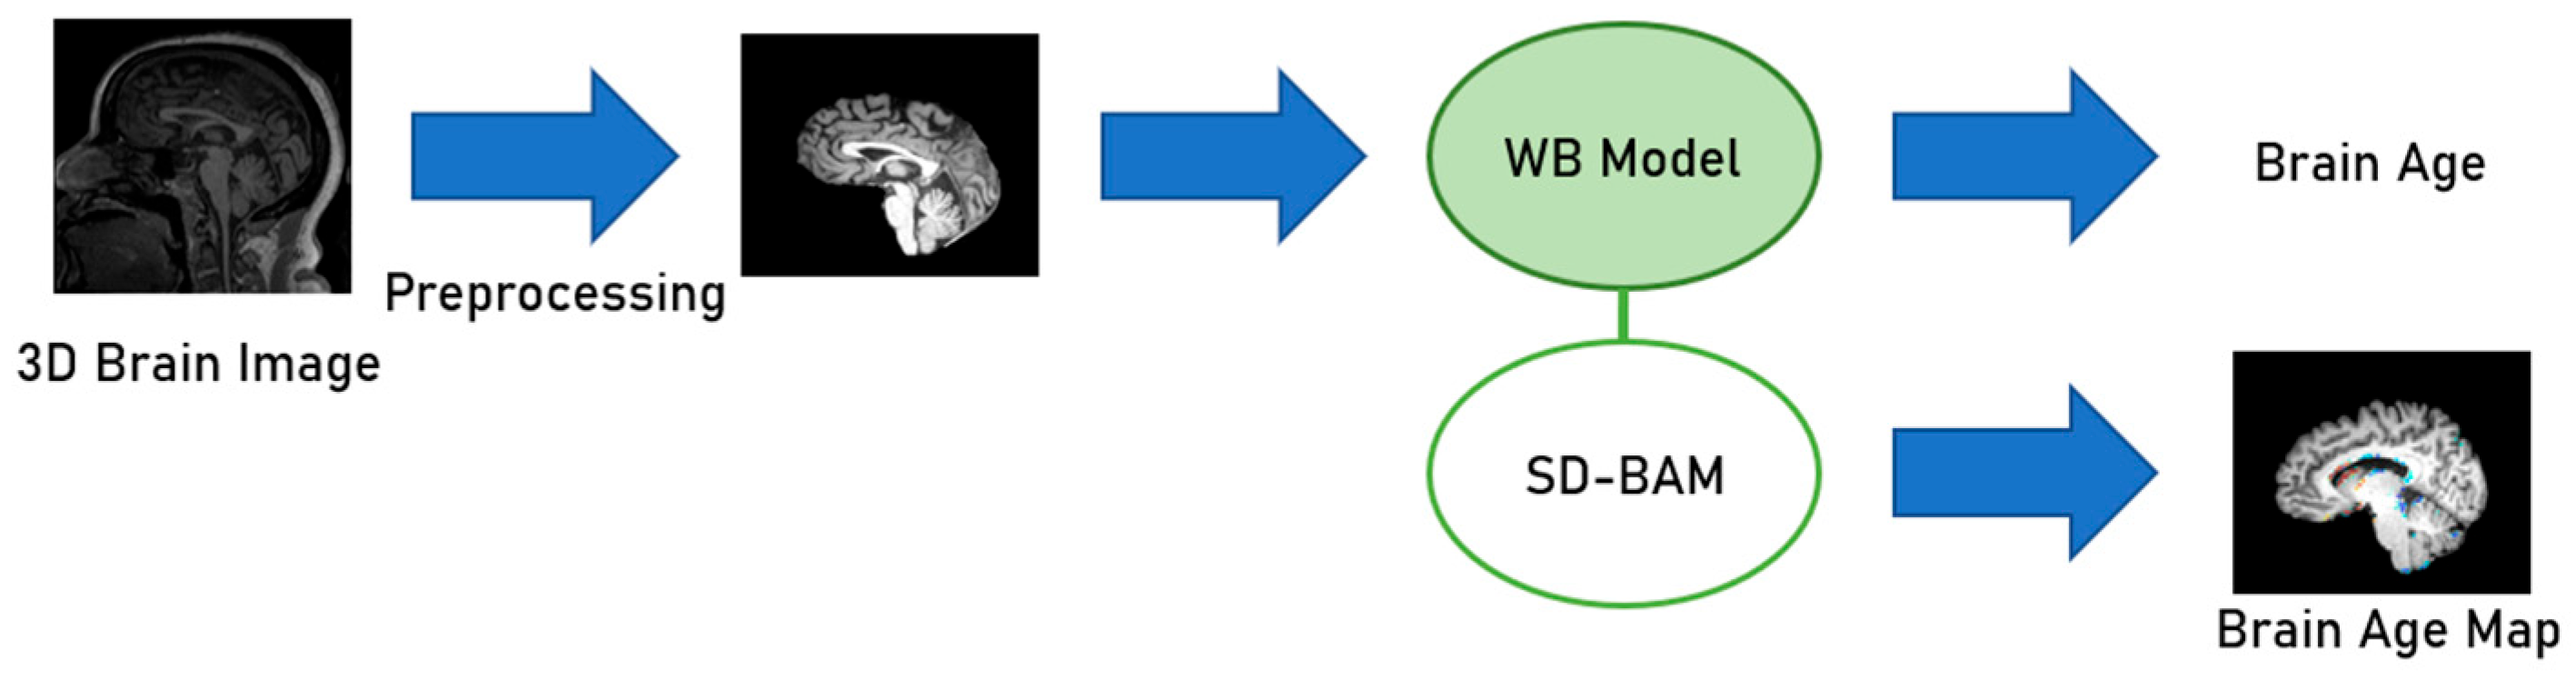

3.3. Model Architecture Design

3.4. Softmax-Derived Brain Age Mapping